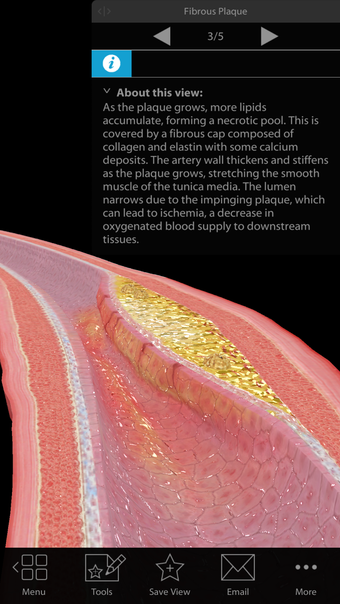

One of the most remarkable features of this application is that it enables users to compare 3D models of normal anatomy with models of common diseases and conditions. Furthermore, users can set the heart rate and visualize conduction in a dissectable, beating 3D heart while following along on an ECG. The application also presents animations that demonstrate the physiological processes of gas exchange, pulmonary ventilation, fluid balance, peristalsis, and more. Interactive lessons walk users through the progression of atherosclerosis, kidney stones, lung cancer, and other common conditions, and quizzes test users' knowledge of various physiological processes and pathologies.